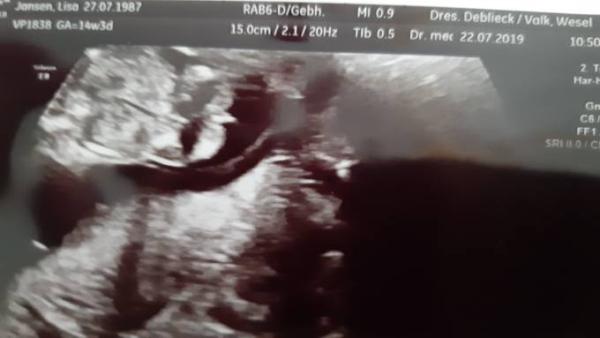

Wir hatten heute einen Termin beim FA und er meinte das Würmchen wäre wohl ein junge allerdings finde ich das der schnippi dann doch Mega groß wäre ! Wie seht ihr das ? Es könnte auch die Nabelschnur oder ein Finger sein !

Bild zu Outing - Forum für Januar - Mamis